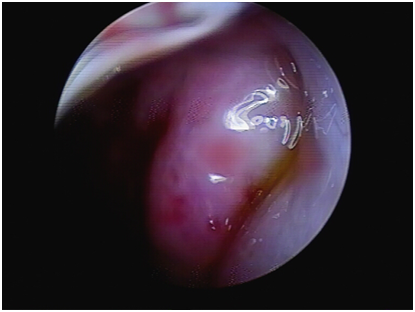

Otoscopic examination revealed hemorrhage in the left tympanic membrane and hemorrhagic effusion in the tympanic chamber (Figure 1A), while the right ear showed no significant abnormality. The nasal endoscope showed a moderate to severe leftward deviation of the nasal septum, squeezing the inferior turbinate, and a significant narrowing of the common nasal passage, with the 4 mm endoscope unable to fully penetrate (Figure 1B). The pharyngo-pharyngeal opening can be seen in the slit of the middle nasal passage, and the shape and activity of the pharyngo-pharyngeal opening can be seen when the patient made swallowing movements (Figure 2). While the right nasal cavity was spacious and well ventilated, and there was no obvious abnormality in the morphology of the pharyngeal orifice of the eustachian tube. CT scan of the ear ruled out cholesterol granuloma of the tympanic chamber and sinus. Laboratory tests showed normal blood count as well as normal coagulation function. Blood pressure was 140/104mmHg (1mmHg=0.133kPa) during HBOT.

Figure 1 (A) Bleeding and fluid accumulation in the tympanic chamber of the left ear on endoscopic examination. (B) Nasal endoscopy revealing a moderate to severe curved left deviation of the nasal septum, compression of the inferior turbinates, and significant narrowing of the common nasal tract.